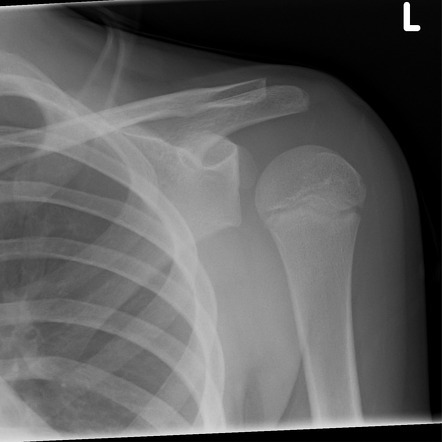

What investigation should be done for a shoulder dislocation?

Plain XR (AP + lat)

What will a AP view plain XR show in an ANTERIOR shoulder dislocation?

- Humeral head visibly out of glenoid fossa (CAN see greater tubercle)

- Humeral head overlaps w other bony structures (aka no GAP)

What will a AP view plain XR show in a POSTERIOR shoulder dislocation? (2 things)

- “Light bulb sign” = humerus fixed in internal rotation (aka CAN’T see greater tubercle)

- Gap between humerus and glenoid (no overlapping)

What is a Lat view plain XR used for in a shoulder dislocation?

To differentiate between ANT + POST dislocations